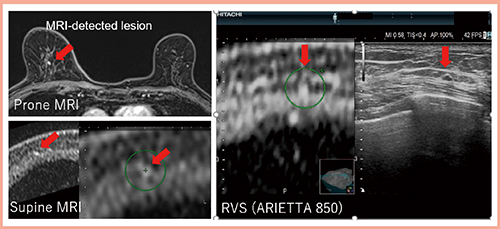

症例1(図2)は,右乳房上方の乳がんに対して広がり診断目的にMRIを施行し,主病巣の乳頭側にMRI-detected lesion(↓)を認めた。通常のSecond-look USでは確認できなかったため,RVSによるSecond-look USを施行した。事前にMR画像上で病変にマーキング(図2○)しておくことで,RVSにてMRIのfocusに一致した低エコー腫瘤を容易に検出することができた(図2右)。針生検の結果は通常型上皮過形成であった。

図2 症例1(72歳):主病巣の乳頭側にMRI-detected lesionを認めた症例